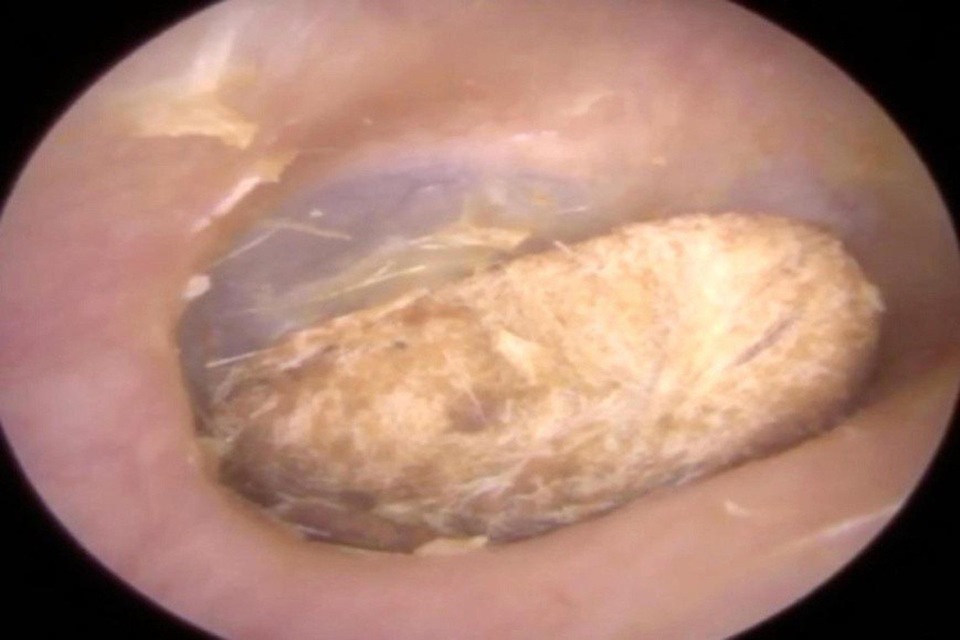

Bệnh nhân nói với bác sĩ tại phòng khám tai rằng từng có một cục bông mắc kẹt trong tai mình 2 năm về trước nhưng anh tin rằng nó đã tự rơi ra không lâu sau đó. Tuy nhiên ngược lại hoàn toàn với điều anh tin tưởng, cục bông vẫn còn ở bên trong và bị ngâm nước trong thời gian bệnh nhân đi bơi gần đây khiến tai anh sưng lên đầy đau đớn.

“Bệnh nhân phàn nàn rằng tai phải giống như bị bóp nghẹt. May mắn là màng nhĩ vẫn còn khỏe mạnh và nguyên vẹn. Mất khoảng 1 phút để loại bỏ cục bông ra khỏi tai. Đó là một công đoạn đầy tinh tế vì cục bông có thể chui vào sâu hơn, làm tổn thương màng nhĩ. Tôi phải đảm bảo rằng mình không tạo ra bất cứ lực nào vì bệnh nhân có thể thủng màng nhĩ nếu tôi làm vậy”, bác sĩ Neel Raithatha chia sẻ.